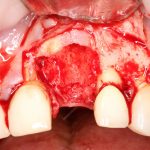

Рекомендации по установке имплантов. Для всех. Часть V.